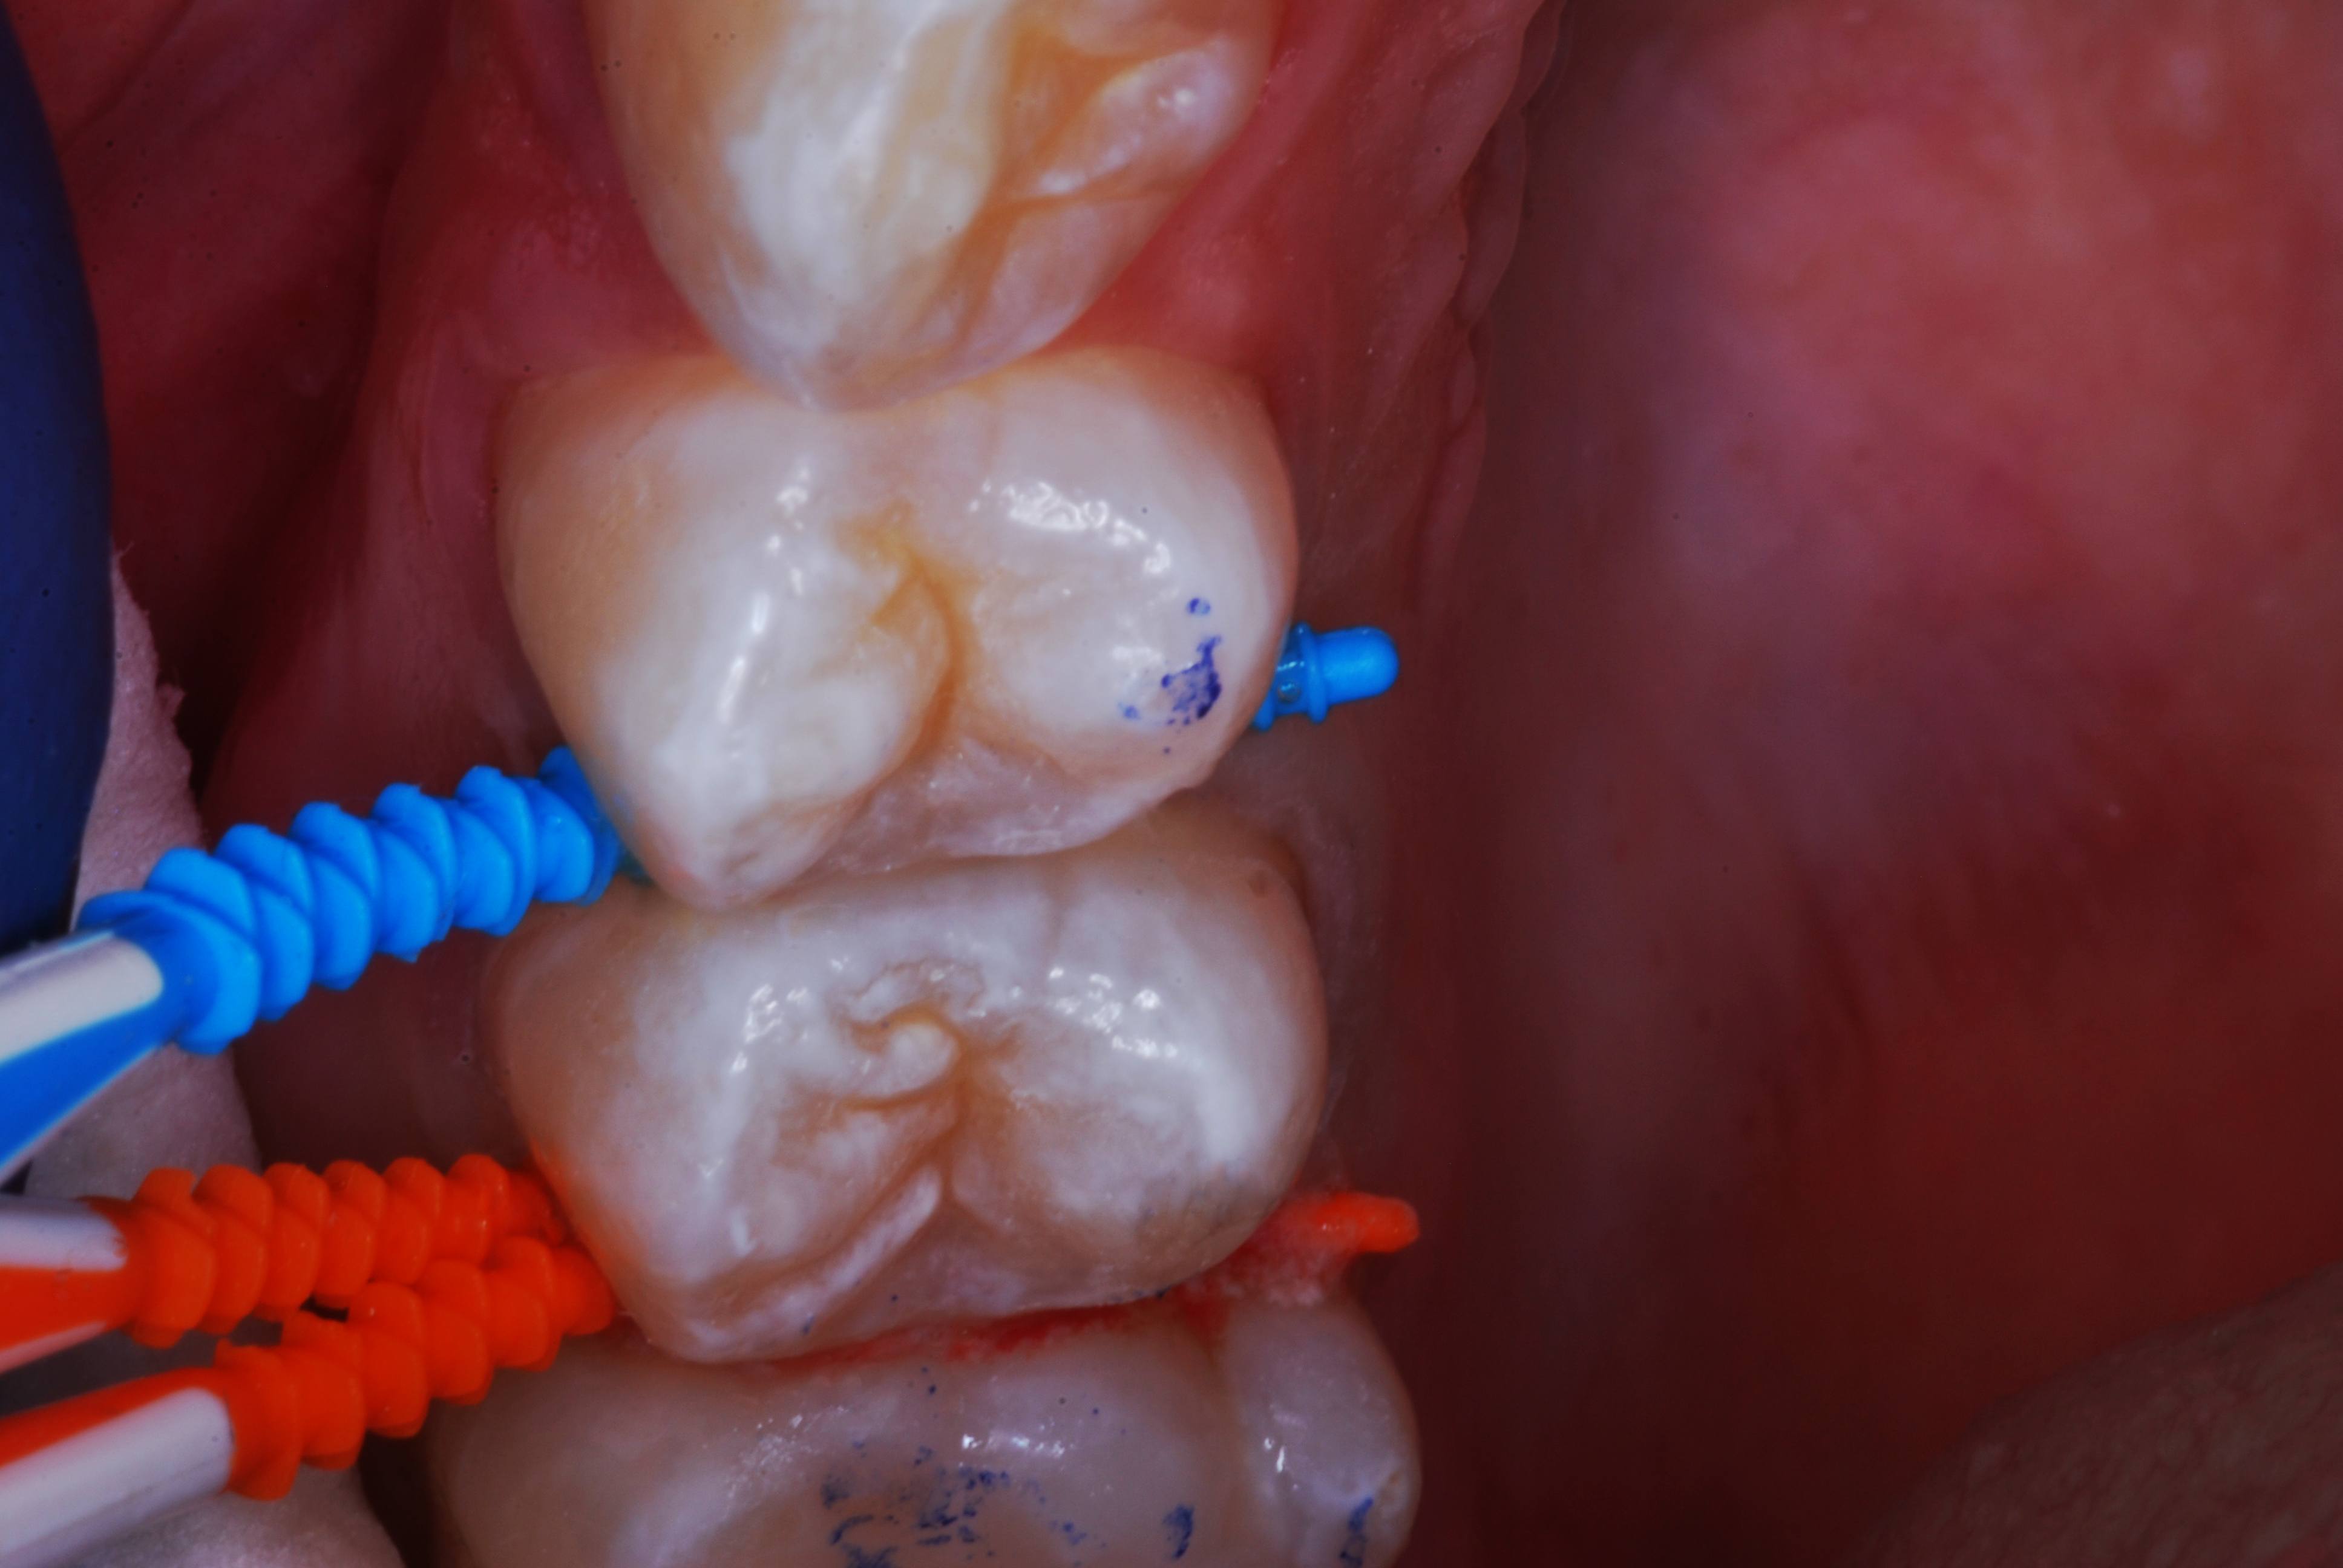

(2.) Lingual and facial maxillary views of 5-year-old patient, 1 year after caries attenuation with SDF. The parents were not concerned about the black staining.

Figure 2

(3.) Lingual and facial maxillary views of 5-year-old patient, 1 year after caries attenuation with SDF. The parents were not concerned about the black staining.

Figure 3